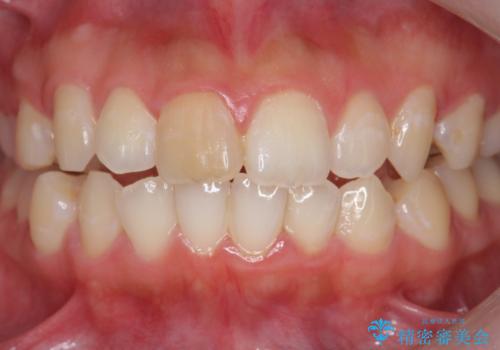

前歯の変色をキレイに セラミッククラウン審美治療

- 前歯の変色が気になる、見た目を改善したい!と審美性の回復を希望され来院されました。

ホワイトニングでは、周囲の歯との色調になじむほどには白くできないため、ジルコニアセラミッククラウンを用いて審美性を回復します。